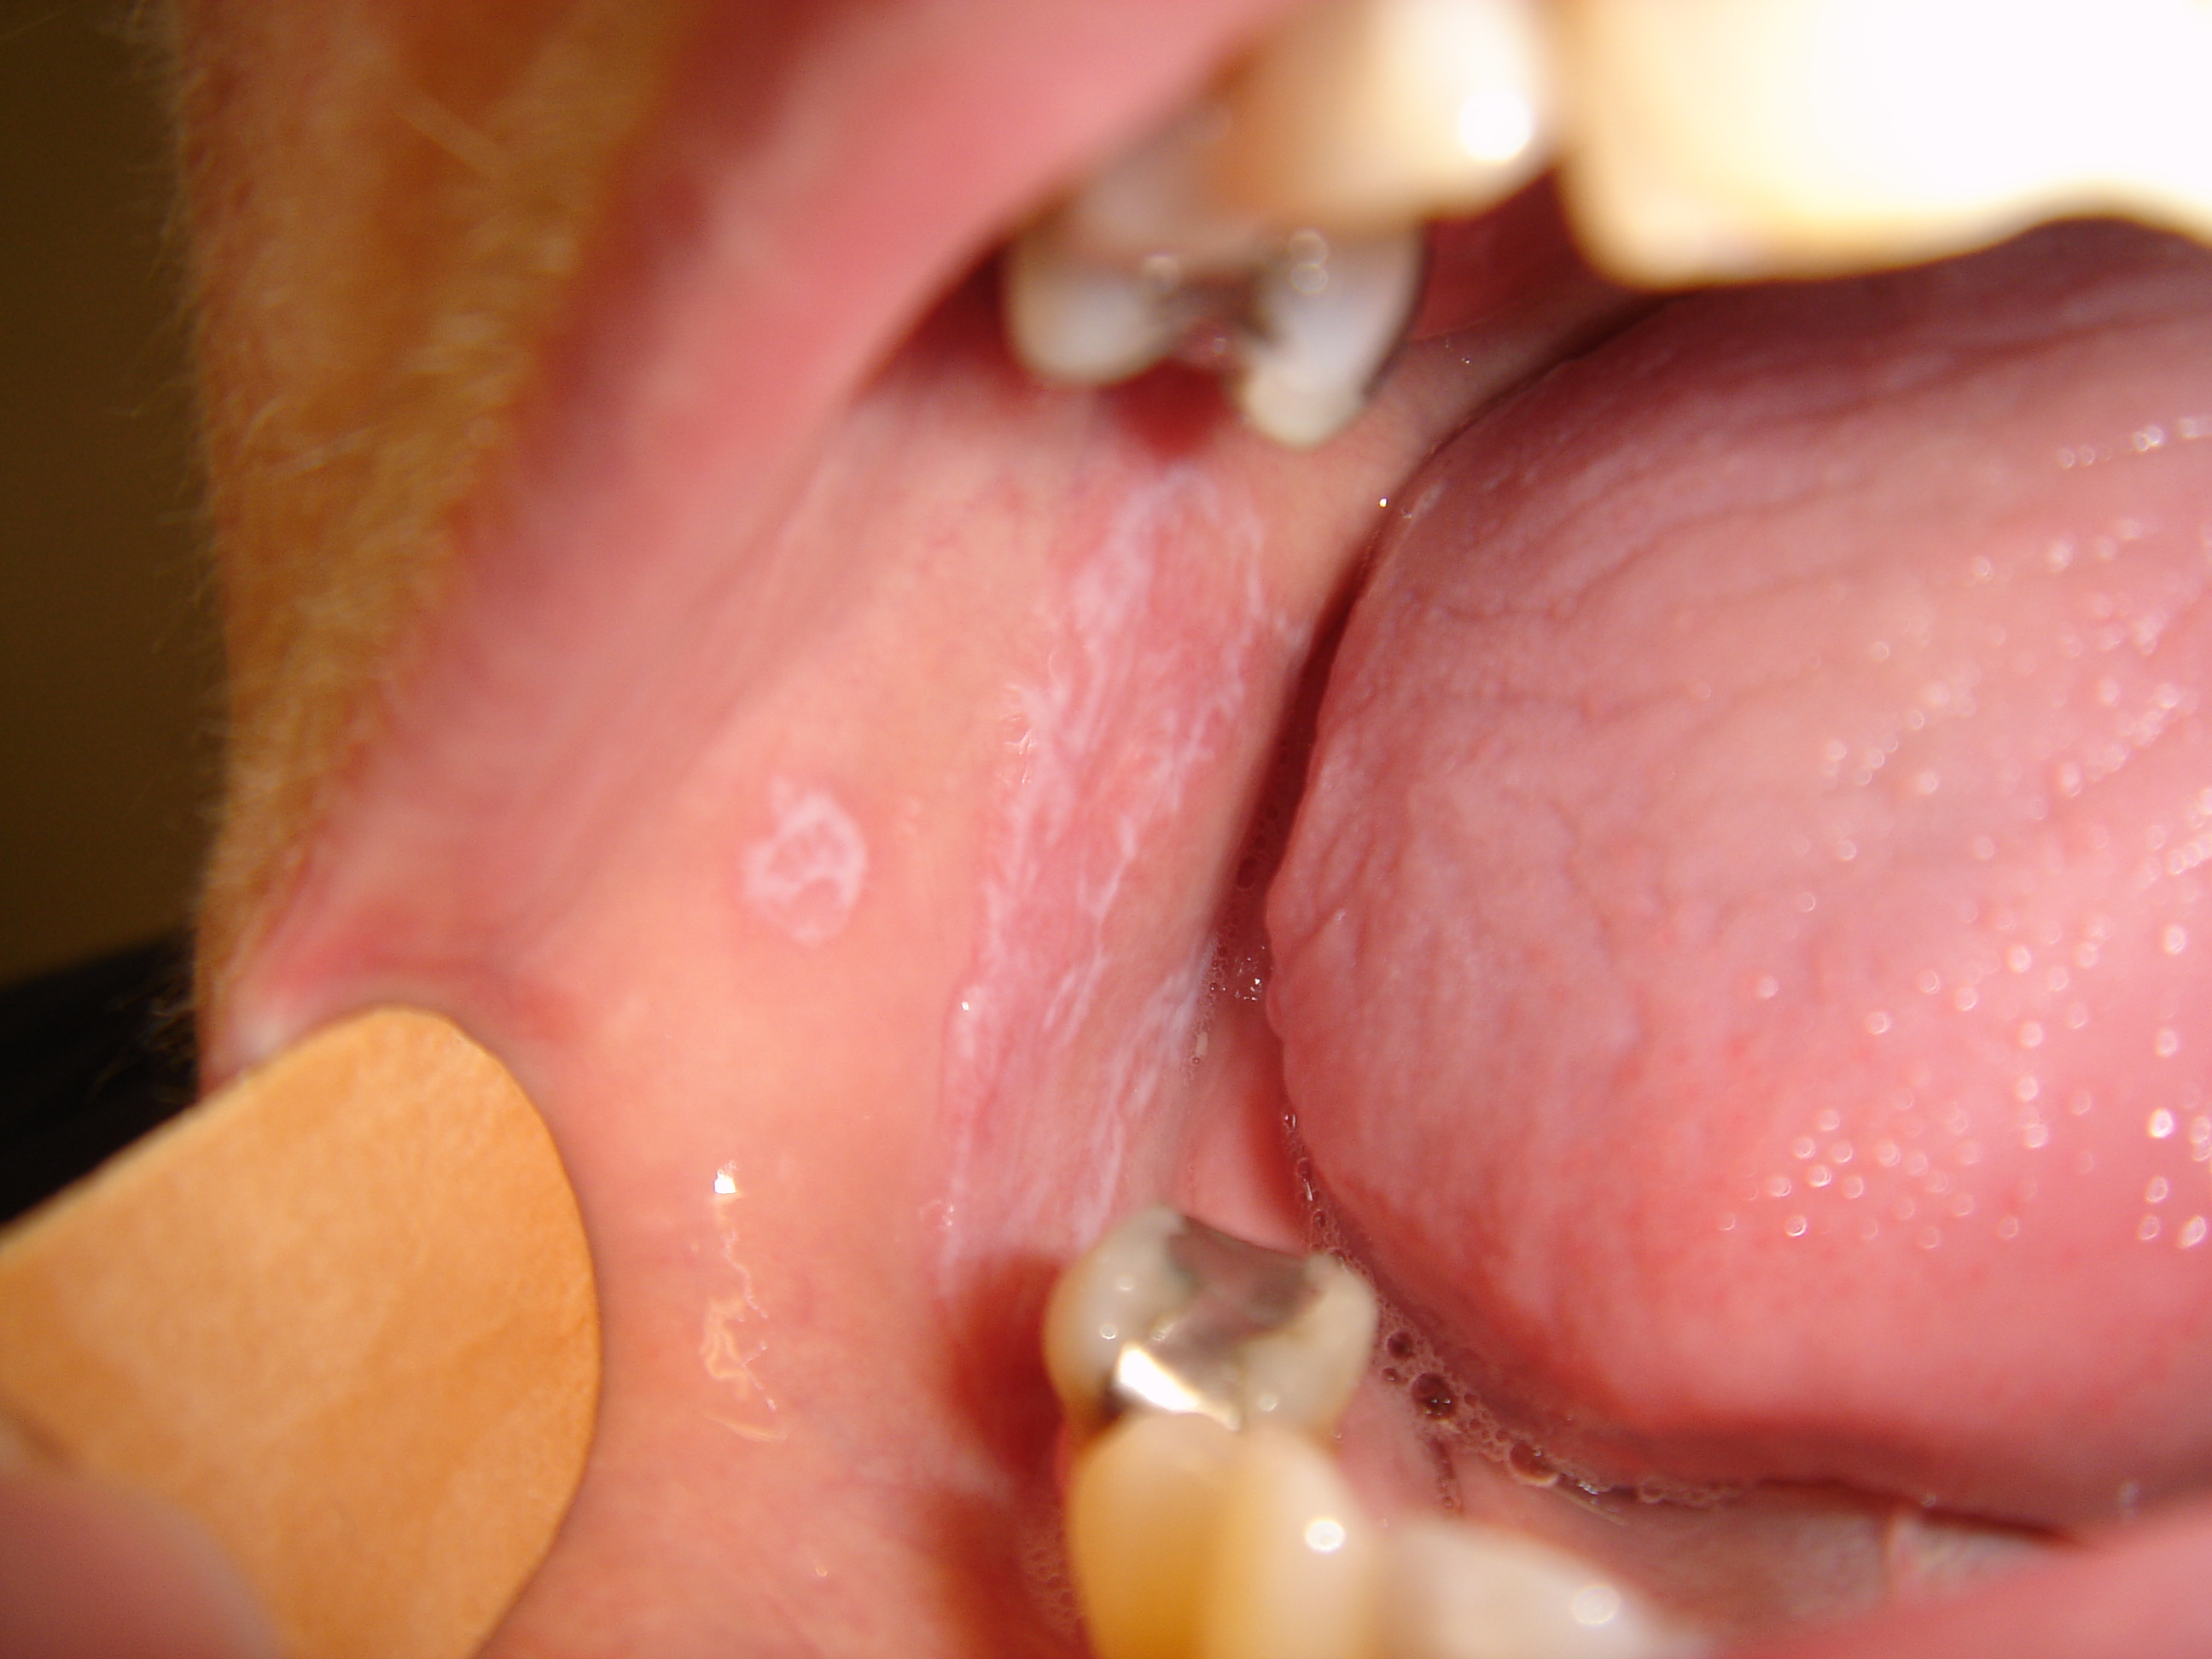

• Hvidlige maculae og striber af netagtig karakter (netmelontegning), som kan udvikle sig til mere atrofiske eller erosive områder. Kindslimhinden er hyppigst afficeret, men tungen, gingiva og læber kan også være ramt

• 15-30 % har kun slimhindeforandringer

Slimhindeforandringer ved lichen planus.

Slimhindeforandringer ved lichen planus forekommer hyppigt og karakteriseres af et netværk af hvide streger (netmelontegning).